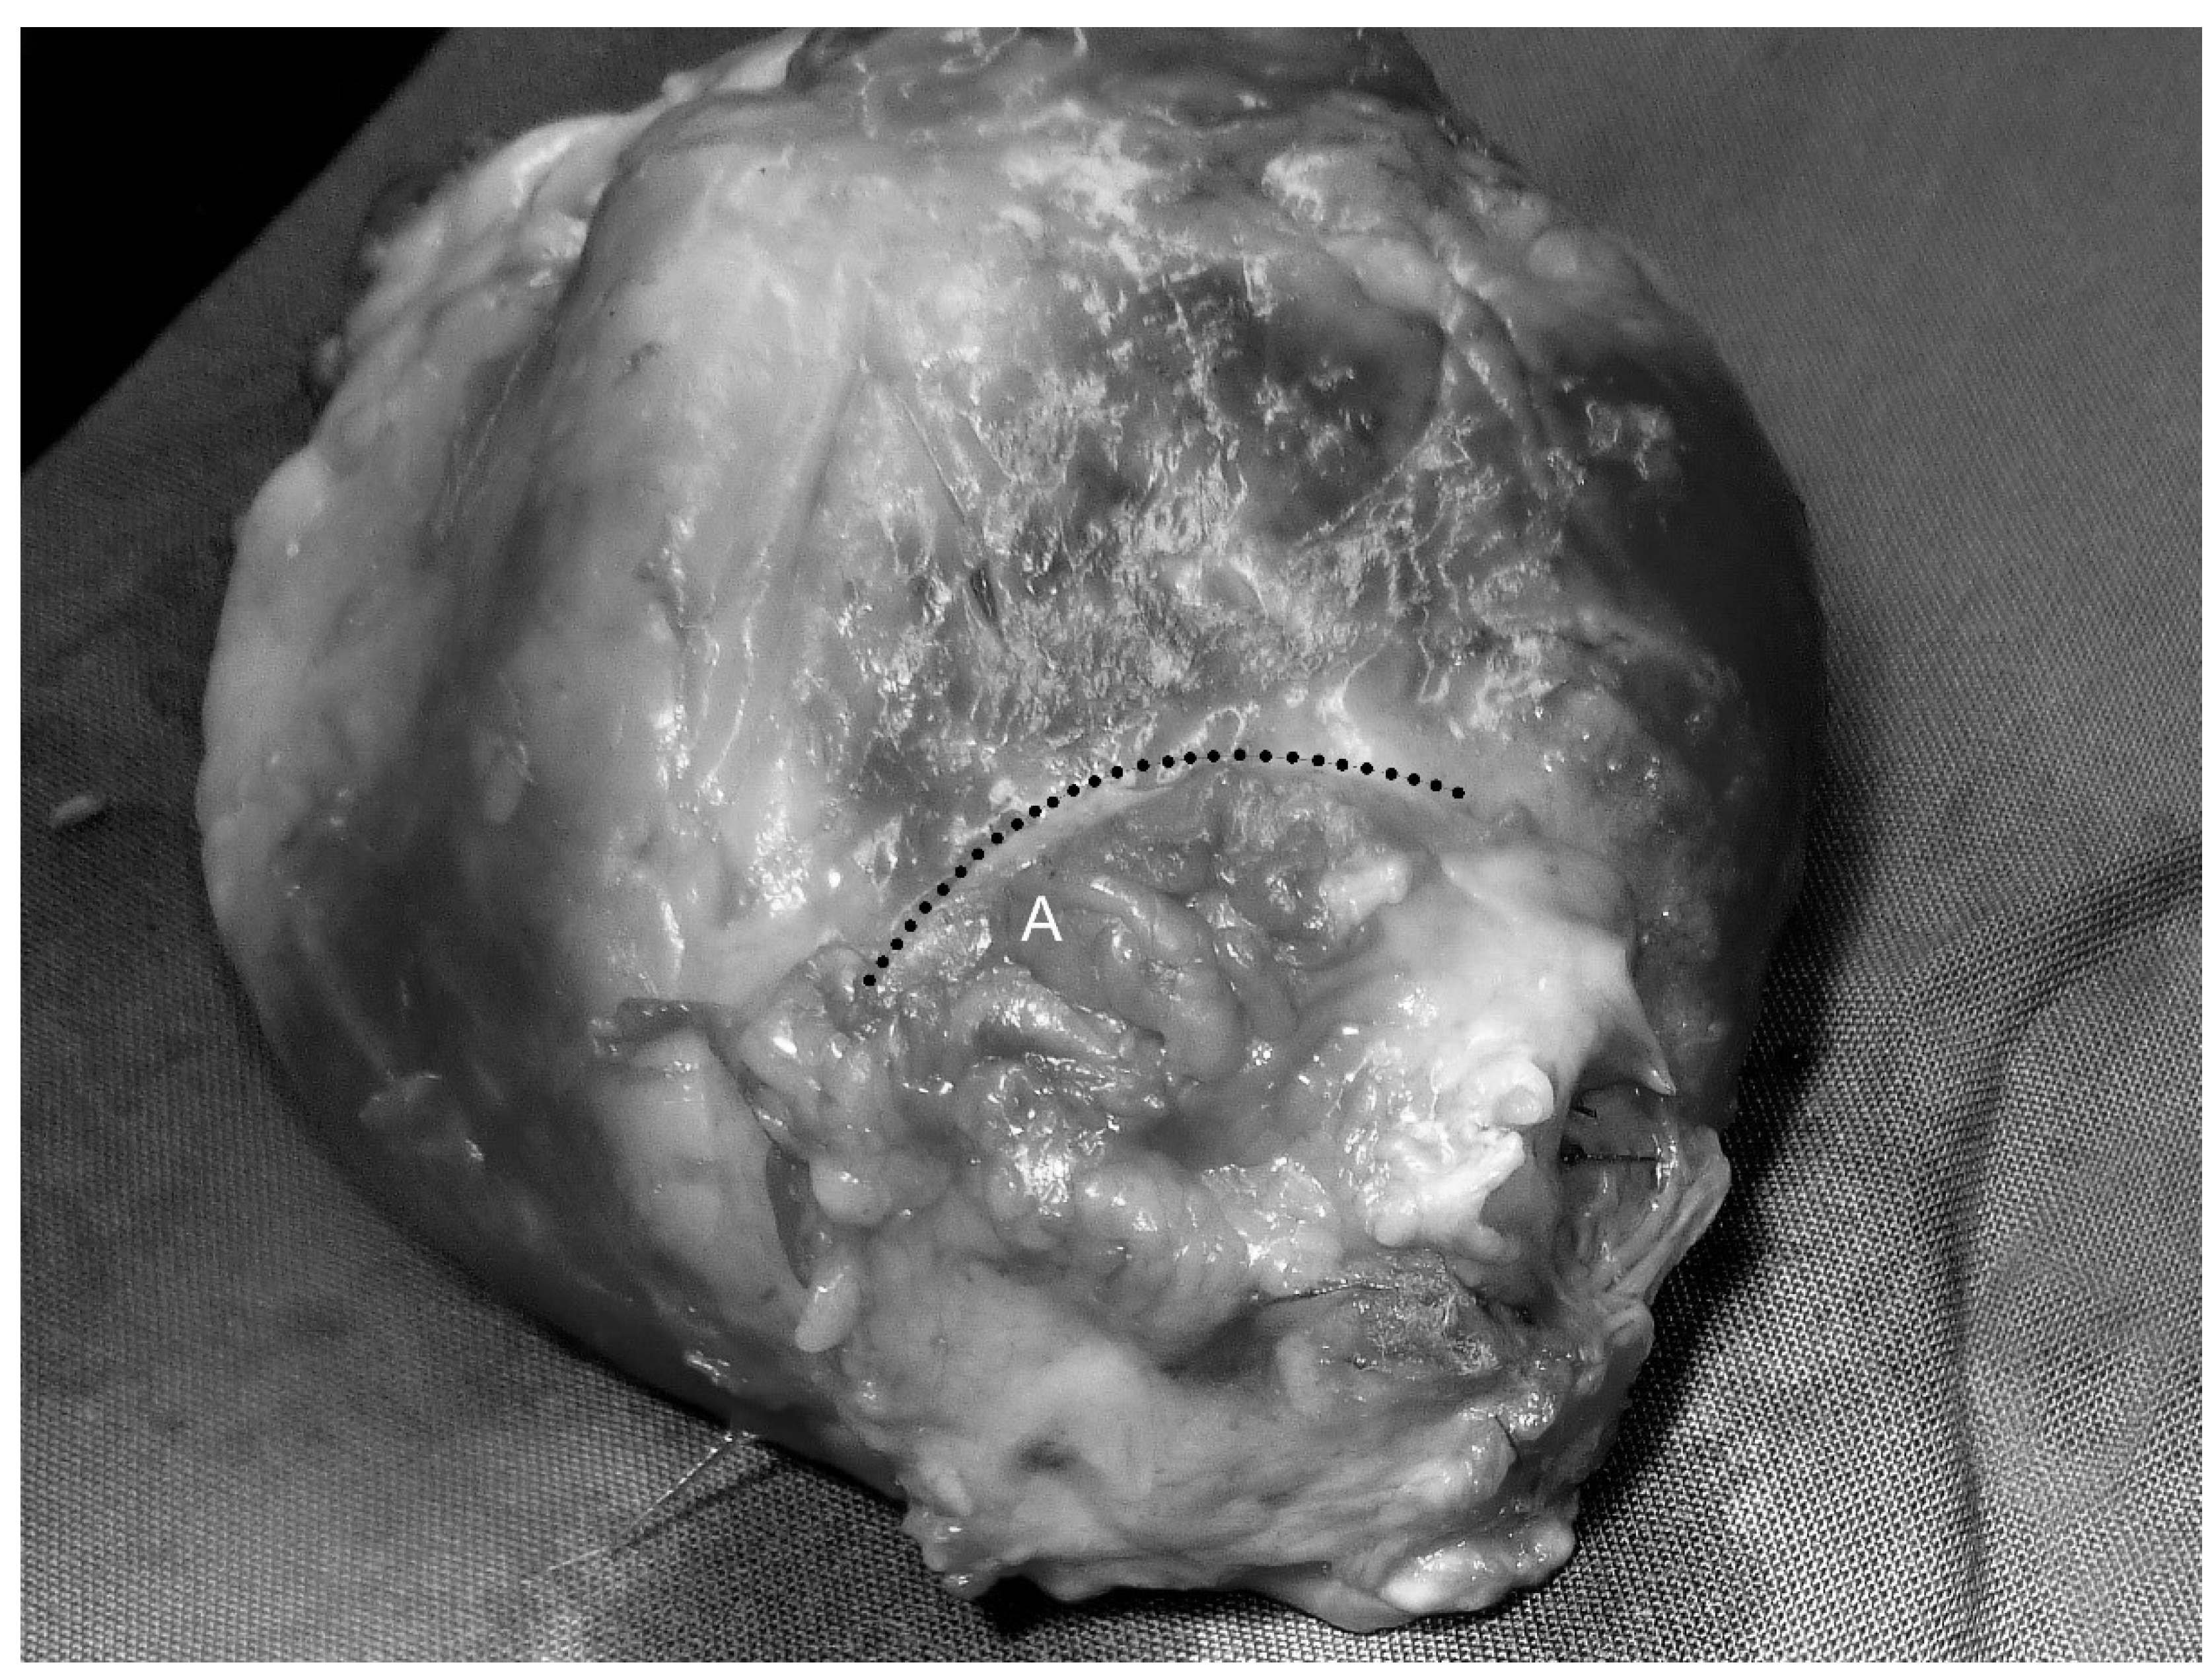

Figure 5.

Explanted heart, including the patch of the decellularized pericardium and autologous vascularized stomach (delineated from the native myocardium by the dotted line, which lies within the cicatricial tissue in the border zone between host tissue and graft) without formation of an aneurysm (A).

There was a confluent endothelialized surface on the luminal side of the implanted pericardium–stomach graft and no evidence of thrombus formation. The border zone between the native myocardium and graft consisted of solid white scar tissue with striated offshoots in the surrounding endocardium (Figure 6).

Figure 6.

Luminal view of the explanted patch of the decellularized pericardium and an autologous vascularized stomach segment (A), surrounded by left ventricular myocardium (B). Smooth and confluent endocardium, no signs of thrombogenesis, no rupture or aneurysm of the graft.